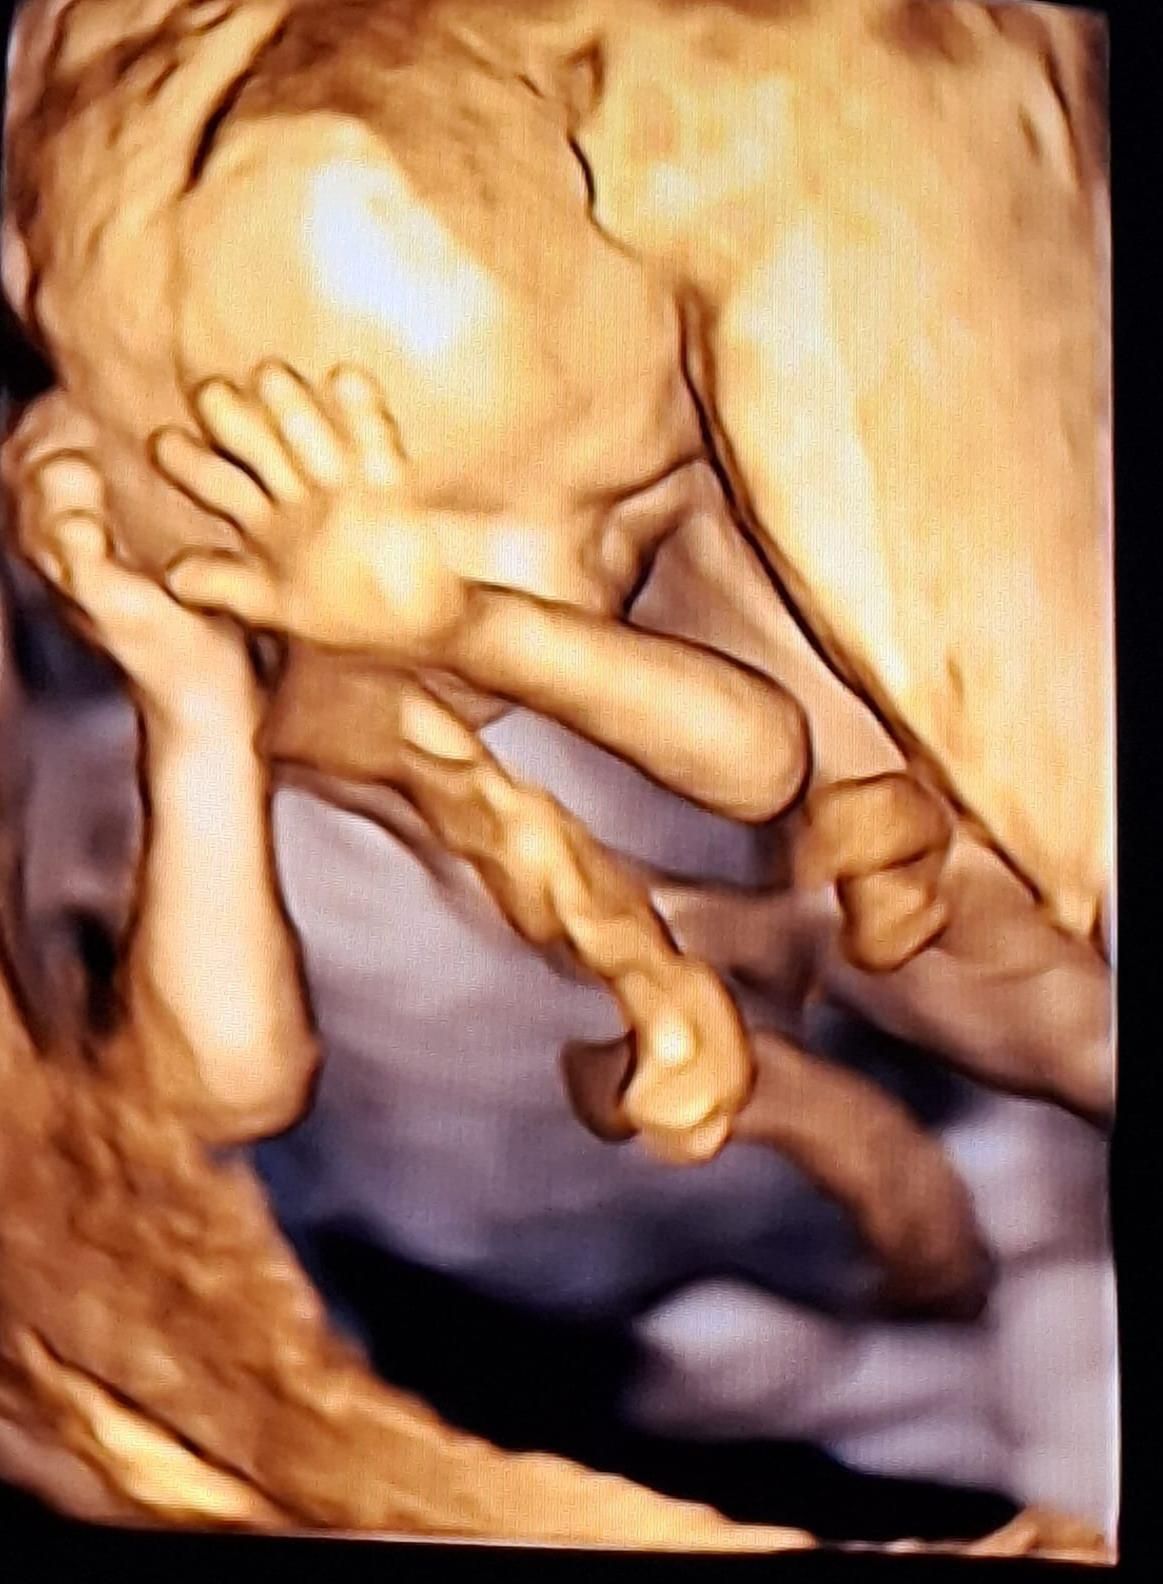

• Ecografie ginecologiche e ostetriche in tutti i trimestri di gravidanza

• Ecografie 3D e valutazioni specifiche tra l’XI e la XIV settimana

• Doppler arterie uterine, controllo dell’accrescimento fetale e velocimetria Doppler

• Ecografia 3D ginecologica e ostetrica

• Ecografia 4D

180 €